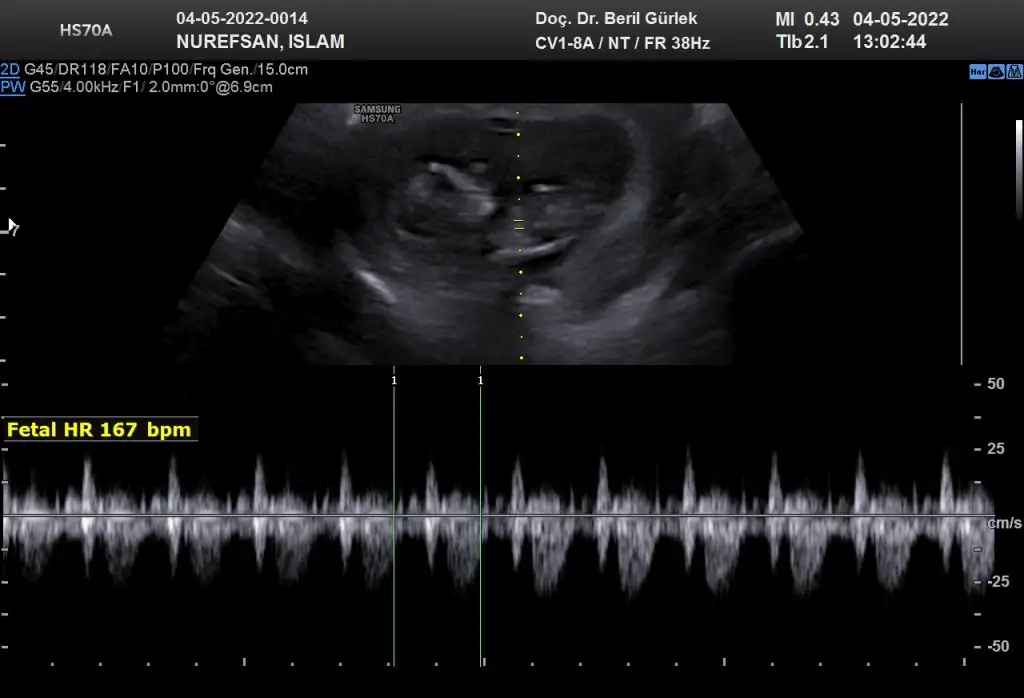

9+5 karından bakıldı banada tahminde bulunur musunuz

erkek gibi11+4 tahmin edebilir misinizzzz